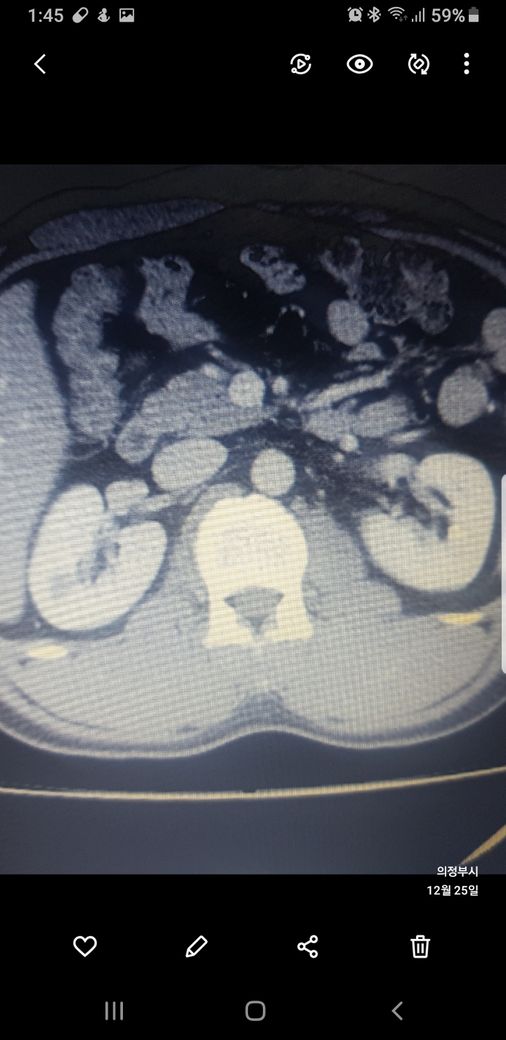

복부ct 작년 11월 , 올해 12월 촬영분입니다.

우측신장에 작년에는 1.7cm 물혹이 올해는 같은곳에 1.2cm 출혈성낭종이라는데

같은부위에 뭐가 다른건지 문제가없는건지 봐주세요.

출혈성낭종은 물혹보단 더 지켜봐야한다는데 왜 같은병원 같은선생님이 다른 소견을 써주셨는지

둘다 같은 병변이고 비조영증강에서 약간의 고음영 소견이 있어 출혈성 낭종이 의심됩니다.

신장의 낭성병변의 분류에서 1, 2, 2F, 3, 4이렇게 나뉘는데, 2에 해당되는 소견입니다.

크게 걱정하실 필요는 없습니다.